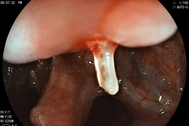

Dấu hiệu nổi mày đay điển hình (Ảnh: Bác sĩ cung cấp).

Biểu hiện thường gặp là các sẩn phù nổi trên da, bao quanh bởi quầng đỏ, gây ngứa dữ dội. Những nốt này có thể tồn tại từ vài chục phút tới hơn một ngày, kích thước từ vài milimet đến vài centimet.